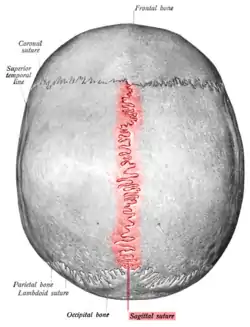

Human adult skull from above. | |

Human adult skull from above. Sagittal suture labeled at center. | |